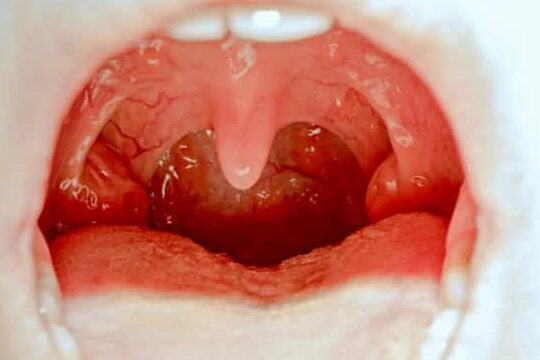

La amigdalitis es una enfermedad infecciosa que causa inflamación de las amígdalas en la garganta. Las amígdalas son estructuras que defienden al organismo de infecciones bacterianas y virales.

- Garganta roja e hinchada.